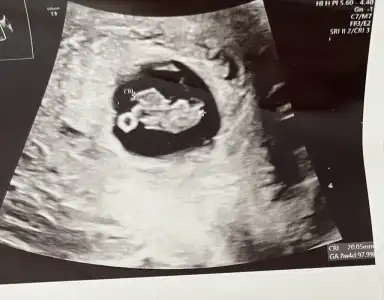

Bana da bakar mısınız? 8+5

• 2C75D14E-3990-4CF1-8F40-999ABD0754FB.webp

2C75D14E-3990-4CF1-8F40-999ABD0754FB.webp

36,2 KB · Görüntüleme: 45